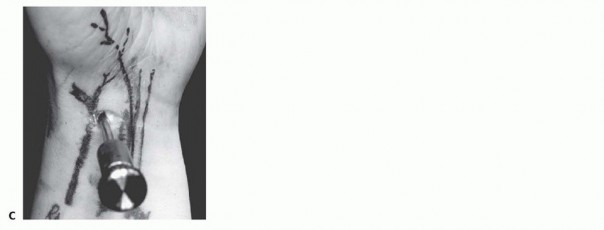

B. Saline injection of radiocarpal joint. C. Insertion of cannula through floor of the FCR sheath. (From Slutsky DJ. Volar portals in wrist arthroscopy. J Am Soc Surg Hand 2002;2:225-232.)